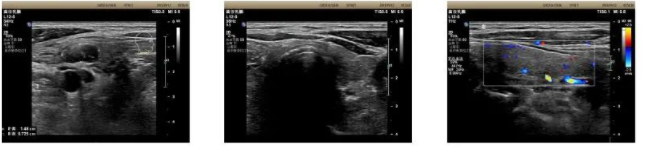

彩超及磁共振检查明确颈部脂肪增生。